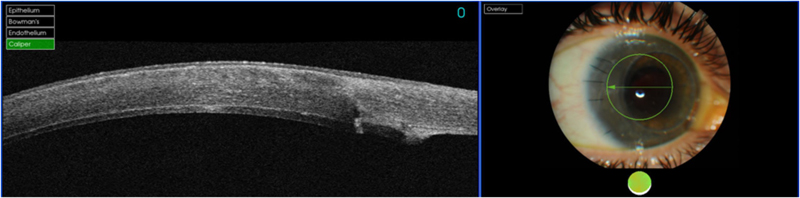

La córnea posee cinco capas histológicamente bien diferenciadas de superficie a profundidad: epitelio, membrana de Bowman, estroma, membrana de Descemet (MD) y endotelio. Las capas de mayor reflectividad en la OCT corresponden a la superficie anterior corneal y al límite posterior de la córnea con la cámara anterior

1. Se puedenobservar corneas sanas (distinguimos epitelio, estroma y endotelio) (

Figura 1). También se pueden estudiar adelgazamientos corneales como el queratocono (

Figura 1. OCT corneal normal.

Figura 2. Vemos la ectasia de un queratocono.

Figura 3. Infección en operado de LASIK.

Figura 4. Resolución de la infección con aposicionamiento del flap.